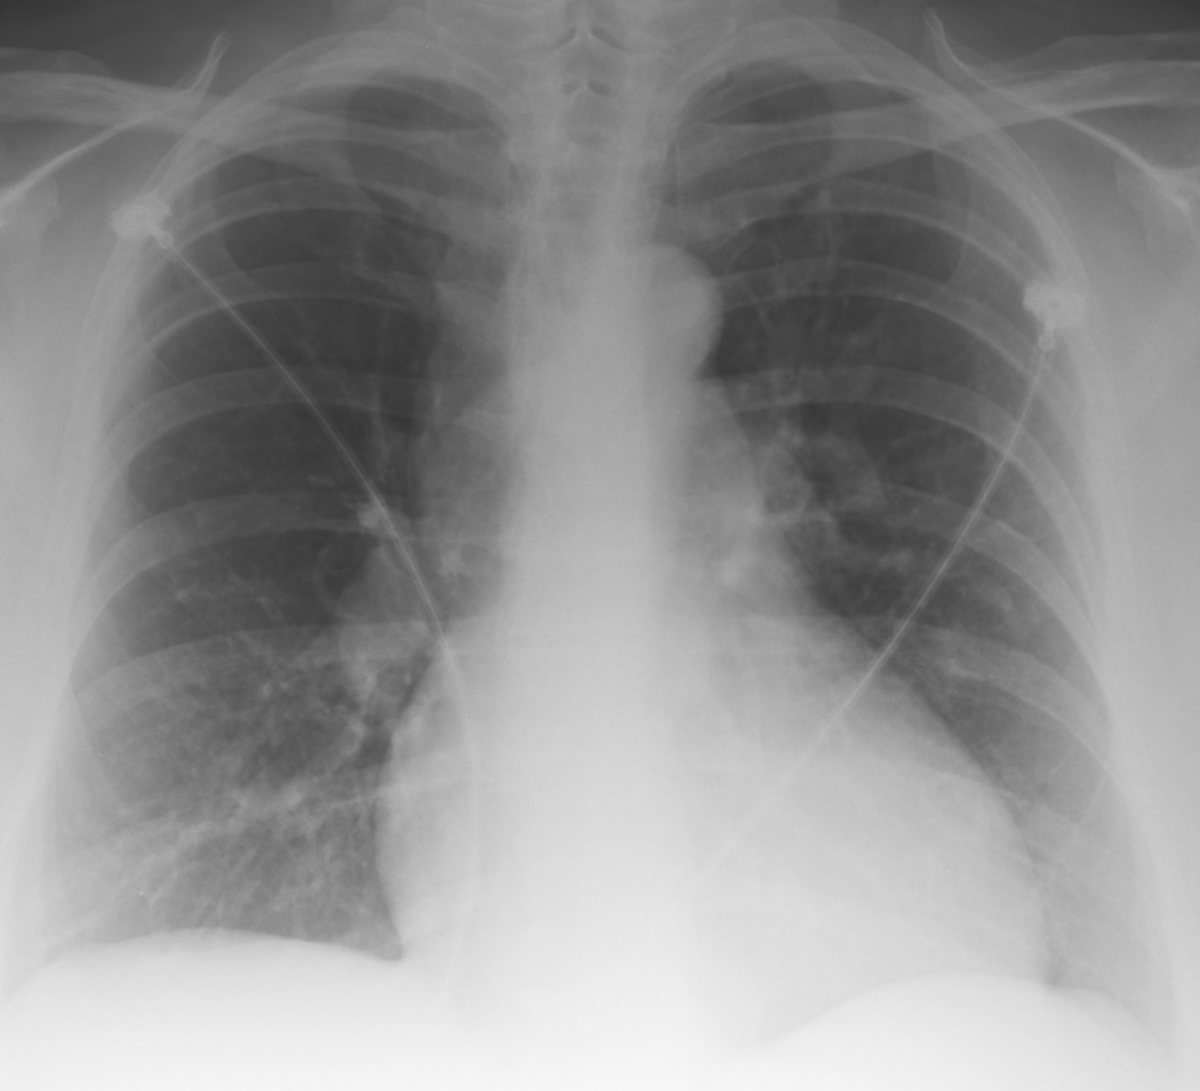

Qual o nome do sinal da primeira figura?

O que indica?

Sinal de WESTERMAK

(oligoemia - hipertransparência - localizada)

Resultado da obstrução ao fluxo sanguíneo naquela região - TEP

Qual o nome deste sinal?

O que significa?

Sinal de HAMPTON

Área de hipotransparência em cunha - local do infarto pulmonar - TEP

Sinal de PALLA

Dilatação do ramo descendente da artéria pulmonar